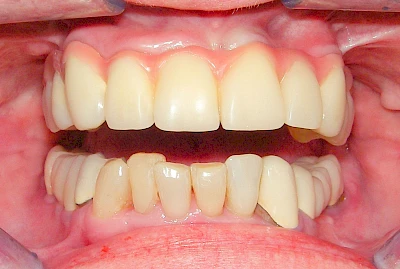

Fehlen einzelne Zähne und die Nachbarzähne sind unbeschadet oder gut zahnärztlich versorgt, werden immer häufiger Implantate gewählt, um die Lücken zu schließen. Auch bei größeren oder verteilten Lücken, wenn keine herausnehmbare Prothese gewünscht ist, werden Implantate für Kronen- bzw. Brückenversorgungen gesetzt. In Einzelfällen entscheiden sich sogar zahnlose Patienten für eine festsitzende Versorgung auf Implantaten.